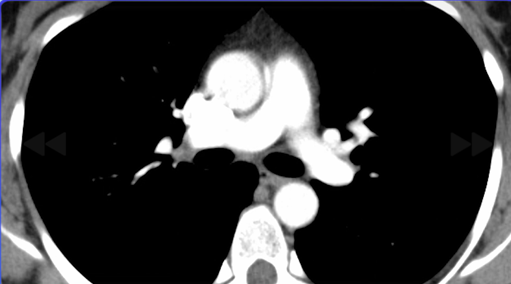

肺動脈相を映した造影CT撮影。

診断:肺動脈血栓症。

しっかり肺動脈相の撮影をすることが重要。